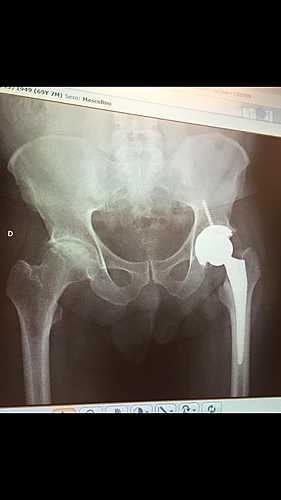

Fiz cirurgia em 2019 para colocação de uma prótese na perna esquerda, conforme foto anexada para que vocês possam ver, no momento preciso colocar a prótese da outra perna.

Muito obrigado. Tem fotos em anexo para que vocês vejam minha situação.